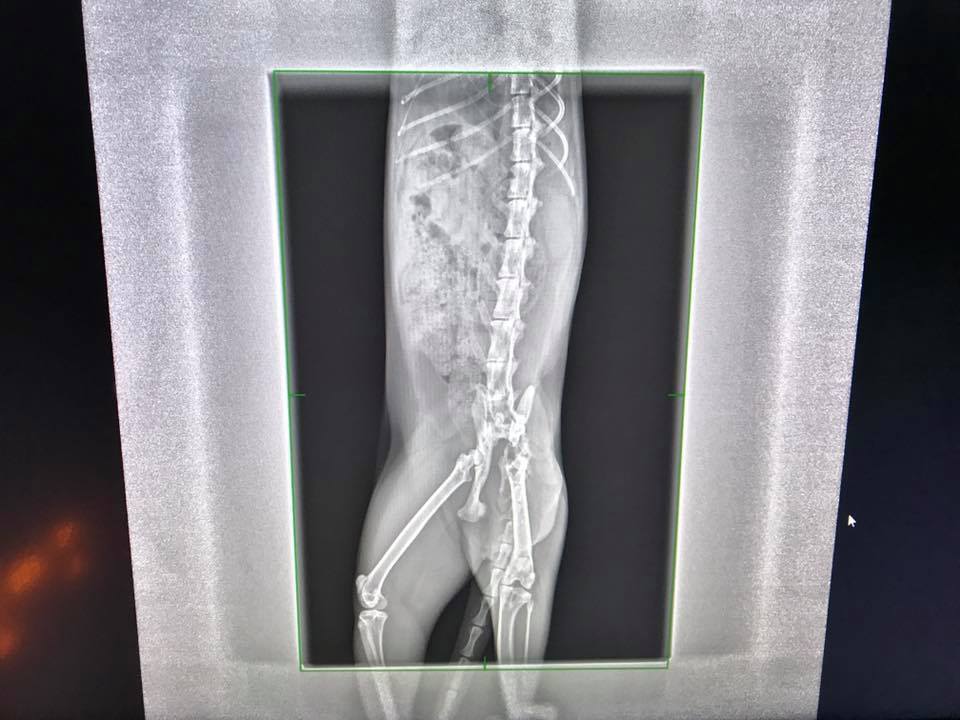

今日回診,因為他出來的大便都是扁的(狹窄還是很嚴重 灌腸時 手指還是被壓住的狀態),X光看附近有長出骨片,但不清楚是否會影響,建議照一下斷層掃描 並且再帶去給亞太看,而且肚子裡的大便也沒有那麼硬,不過腸子確實也變寬了,目前先取消楊車前子粉,讓肚子的便便先趕快排出